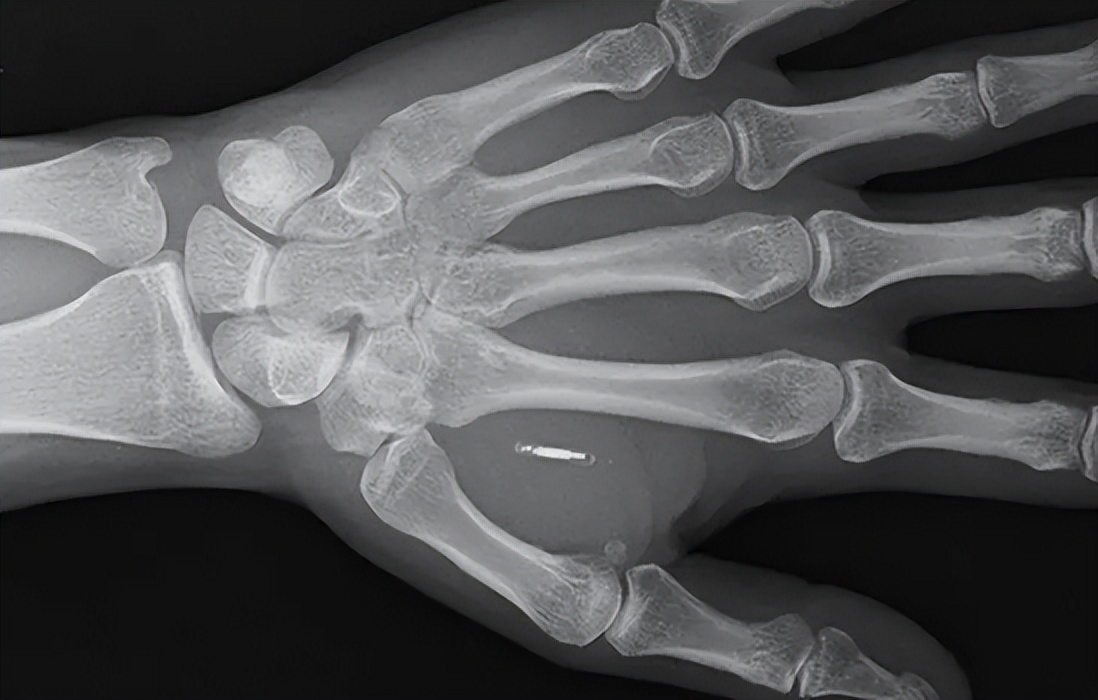

據(ju)Walletmor公司介(jie)紹,這種植(zhi)入支付芯(xin)(xin)(xin)片(pian)重量不到(dao)(dao)(dao)一(yi)克(ke),比(bi)一(yi)粒米大一(yi)點。它是(shi)由一(yi)個(ge)(ge)微(wei)型芯(xin)(xin)(xin)片(pian)和一(yi)個(ge)(ge)天線(xian)圈(quan)組成(cheng),包裹(guo)在(zai)(zai)(zai)類似于塑料的(de)天然(ran)生物聚(ju)合(he)物中。平常感(gan)(gan)受(shou)不到(dao)(dao)(dao)芯(xin)(xin)(xin)片(pian)的(de)存在(zai)(zai)(zai),但在(zai)(zai)(zai)付款(kuan)的(de)時候,會(hui)感(gan)(gan)覺到(dao)(dao)(dao)像是(shi)有人“捏你(ni)的(de)皮膚”,并(bing)且能(neng)感(gan)(gan)受(shou)到(dao)(dao)(dao)手(shou)部輕微(wei)的(de)震動。芯(xin)(xin)(xin)片(pian)植(zhi)入人體后能(neng)立即起作用,并(bing)會(hui)牢(lao)牢(lao)固定(ding)在(zai)(zai)(zai)原(yuan)位。此外,它也不需要任何充電裝(zhuang)置。